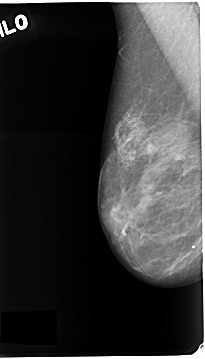

C_0123_1.LEFT_MLO

LEFT_MLO LINES 4688 PIXELS_PER_LINE 2424 BITS_PER_PIXEL 12 RESOLUTION 50 OVERLAY